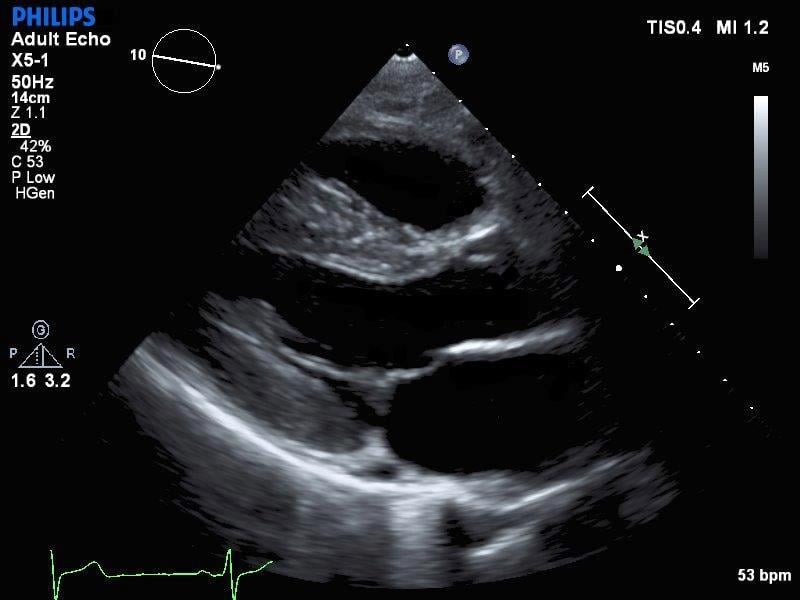

EPIQ Evolution 2.0, released in the summer, enhances image quality specifically for vascular, breast, vaginal, and cardiac applications. But EPIQ can handle any radiological, cardiological, or OB/GYN application.

Like sonography itself, EPIQ is evolving, as evidenced by the summer 2016 release of a new version. This new release improves image quality in vascular, breast, and 3-D vaginal applications, as well as provides Live 3-D quantification and automated 2-D views in echocardiography. It also increases security to help protect patient data from hackers, and provides an “ecosystem” of tools, applications, and solutions, called OmniSphere, to boost business efficiency and optimize operations.